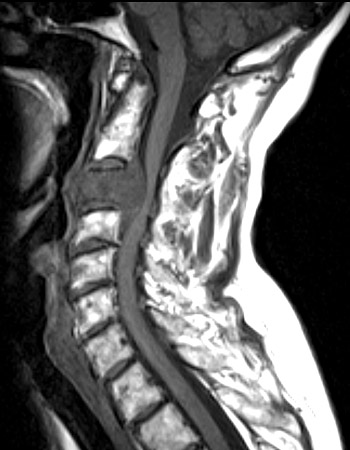

The sagittal MRI scan above demonstrates a

destructive mass

which is a chordoma that is destroying the C2 vertebral body and

impinging upon the spinal cord

. Another sagittal view with T2 weighting, and an axial view appear below.